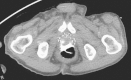

Radiation therapy is a widely utilized treatment modality for pelvic malignancies, including prostate cancer, rectal cancer, and cervical cancer. Given its fixed position in the pelvis, the rectum is at a high risk for injury secondary to ionizing radiation. Despite advances made in radiation science, up to 75% of the patients will suffer from acute radiation proctitis and up to 20% may experience chronic symptoms. Symptoms can be variable and include diarrhea, bleeding, incontinence, and fistulization. A multitude of treatment options exist. This article summarizes the latest knowledge relating to radiation proctopathy focusing on the vast array of treatment options.